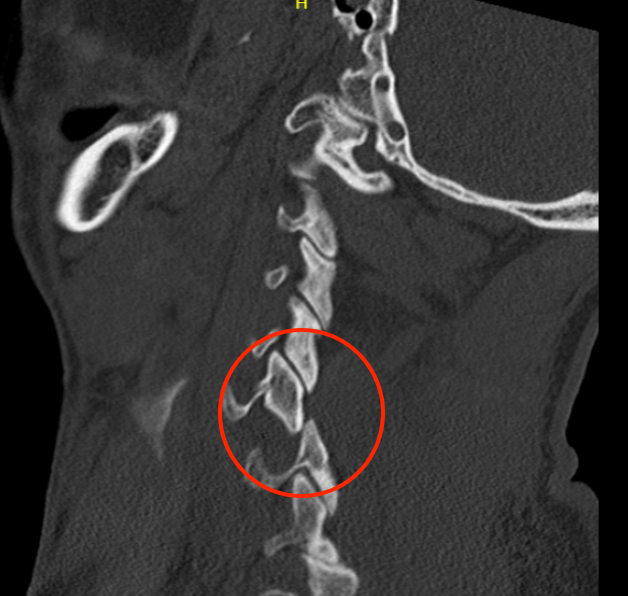

Unilateral facet joint dislocation on CT

Bilateral jumped facets on CT